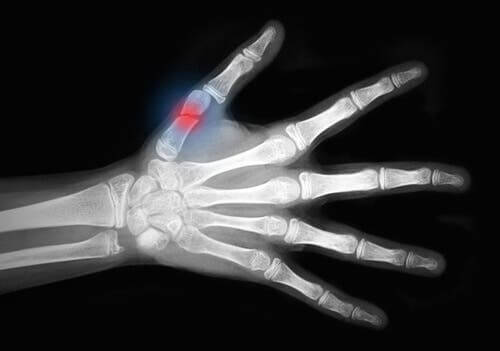

In the medical field, degloving injuries are traumatic injuries that rip the soft tissues of the skin over large areas and expose the bone. These mainly affect the extremities.

Finally, there are grade III injuries. These injuries are associated with severe skin and muscle damage, such as:

- Vascular injuries.

- Acute compartment syndromes. This is a serious condition that involves increased pressure in a muscle compartment. It can lead to nerve and muscle damage, as well as blood flow problems.

- Crush injuries.

- Degloving injuries.

As you can see, degloving injuries belong to the most serious group of soft tissue injuries.